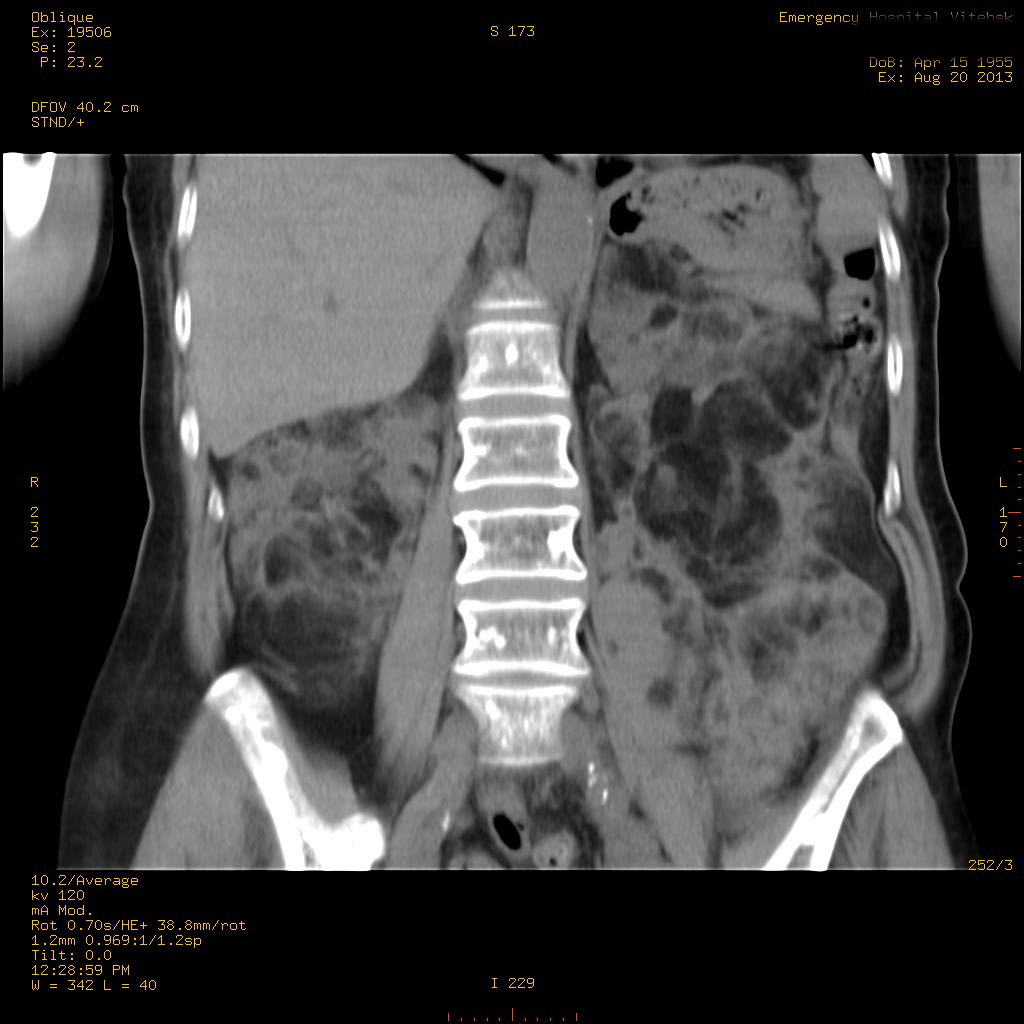

Пожилая женщина с нормальными мочевиной и креатинином.

Ангиомиолипоматоз почек , думаю компонент туберозного склероза.

Да, туберозный склероз.

Случай консультирован на кафедре радиологии Католического университета г.Лёвен (Бельгия) - зав каф. профессор Р.Оуен.